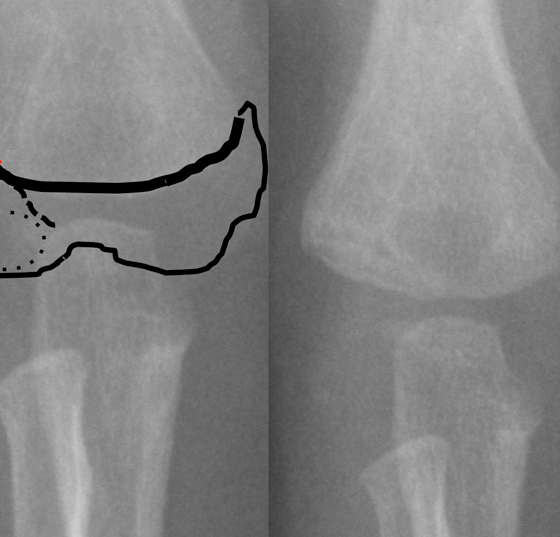

• Zweiter Teil: Kindertraumatologie für die Praxis

Frakturen der unteren Extremitäten

An den unteren Extremitäten ist die häufigste Lokalisation für eine Fraktur der Unterschenkel (11,4%), wobei 7% den distalen Unterschenkel betreffen. Oberschenkelfrakturen sind mit 2,9% recht selten. Was sollte man in...…